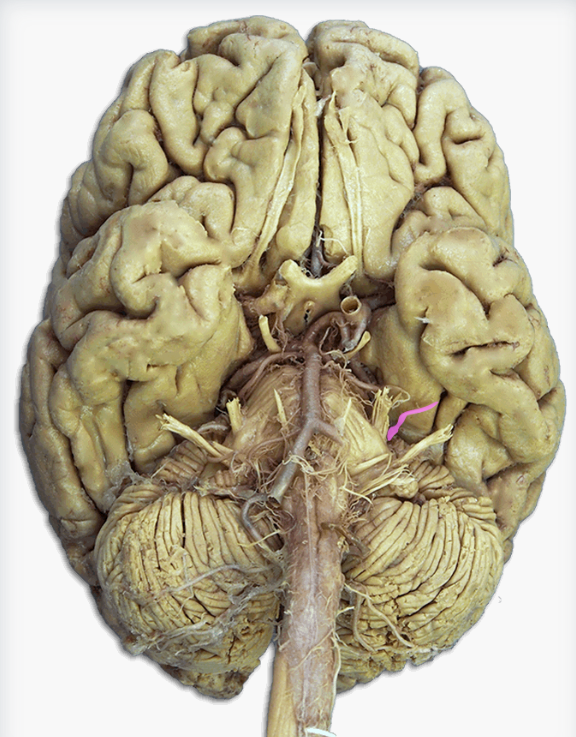

What is this?

Anterior cerebral artery

Label this structure

Hypoglossal (CN XII) nerve

Label this cranial nerve

Olfactory (CN I) nerve

Label this cranial nerve

Optic (CN II) nerve

Label this cranial nerve

Oculomotor (CN III) nerve

Label this cranial nerve

Trochlear (CN IV) nerve

Label this cranial nerve

Trigeminal (CN V) nerve

Label this cranial nerve

Abducens (CN VI) nerve

Label this cranial nerve

Facial (CN VII) nerve

Label this cranial nerve

Vestibulocochlear (VIII) nerve

Label this cranial nerve

Glossopharyngeal (CN IX) nerve

Label this cranial nerve

Vagus (CN X) nerve

Label this cranial nerve

Accessory (CN XI) nerve

Label this cranial nerve

Hypoglossal (CN XII) nerve